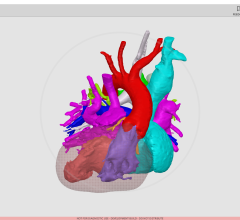

NIH researchers found that dark rimmed spots representing ongoing, “smoldering” inflammation, may be a hallmark of more disabling forms of multiple sclerosis. Image courtesy of Reich lab, NIH/NINDS.

To do this, the team scanned the brains of 192 multiple sclerosis patients who had entered a trial at the NIH’s Clinical Center. They found that, regardless of the treatment they were receiving, 56 percent of the patients had at least one rimmed lesion. Further analysis showed that 44 percent of patients had only rimless lesions; 34 percent had one to three rimmed lesions; and 22 percent had four or more rimmed lesions.

They then compared the brain scans to the neurological examinations the patients received upon enrollment. Patients who had four or more rimmed lesions were 1.6 times more likely to be diagnosed with progressive MS than those without rimmed lesions. Moreover, these patients developed motor and cognitive disabilities at a younger age than the patients who had no rimmed lesions. When the researchers analyzed key parts of the patients’ brains, they found that patients who had four or more rimmed lesions had less white matter and smaller basal ganglia than those who had no rimmed lesions.

The team then analyzed a subset of patients whose brains had been scanned once every year for 10 years or longer. Their results suggested that, while the rimless lesions generally shrank, the rimmed lesions either grew or stayed the same size and were particularly damaged.

Finally, the team used a 3-D printer to compare the spots they had seen on scans to the lesions they observed in brain tissue samples autopsied from a patient who had passed away during the trial. They found that all expanding rimmed spots seen on the scans had the telltale features of chronic active lesions when examined under a microscope.